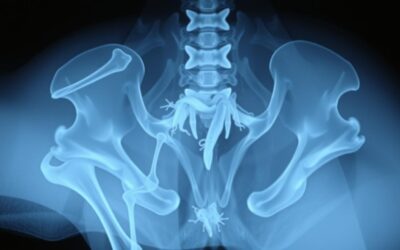

Prijelom zdjelice kod mačaka – Sve što trebaš znati o tome!

Razumijemo brige oko prijeloma zdjelice kod mačaka. Otkrijte uzroke, simptome i metode liječenja ovog ozbiljnog stanja.